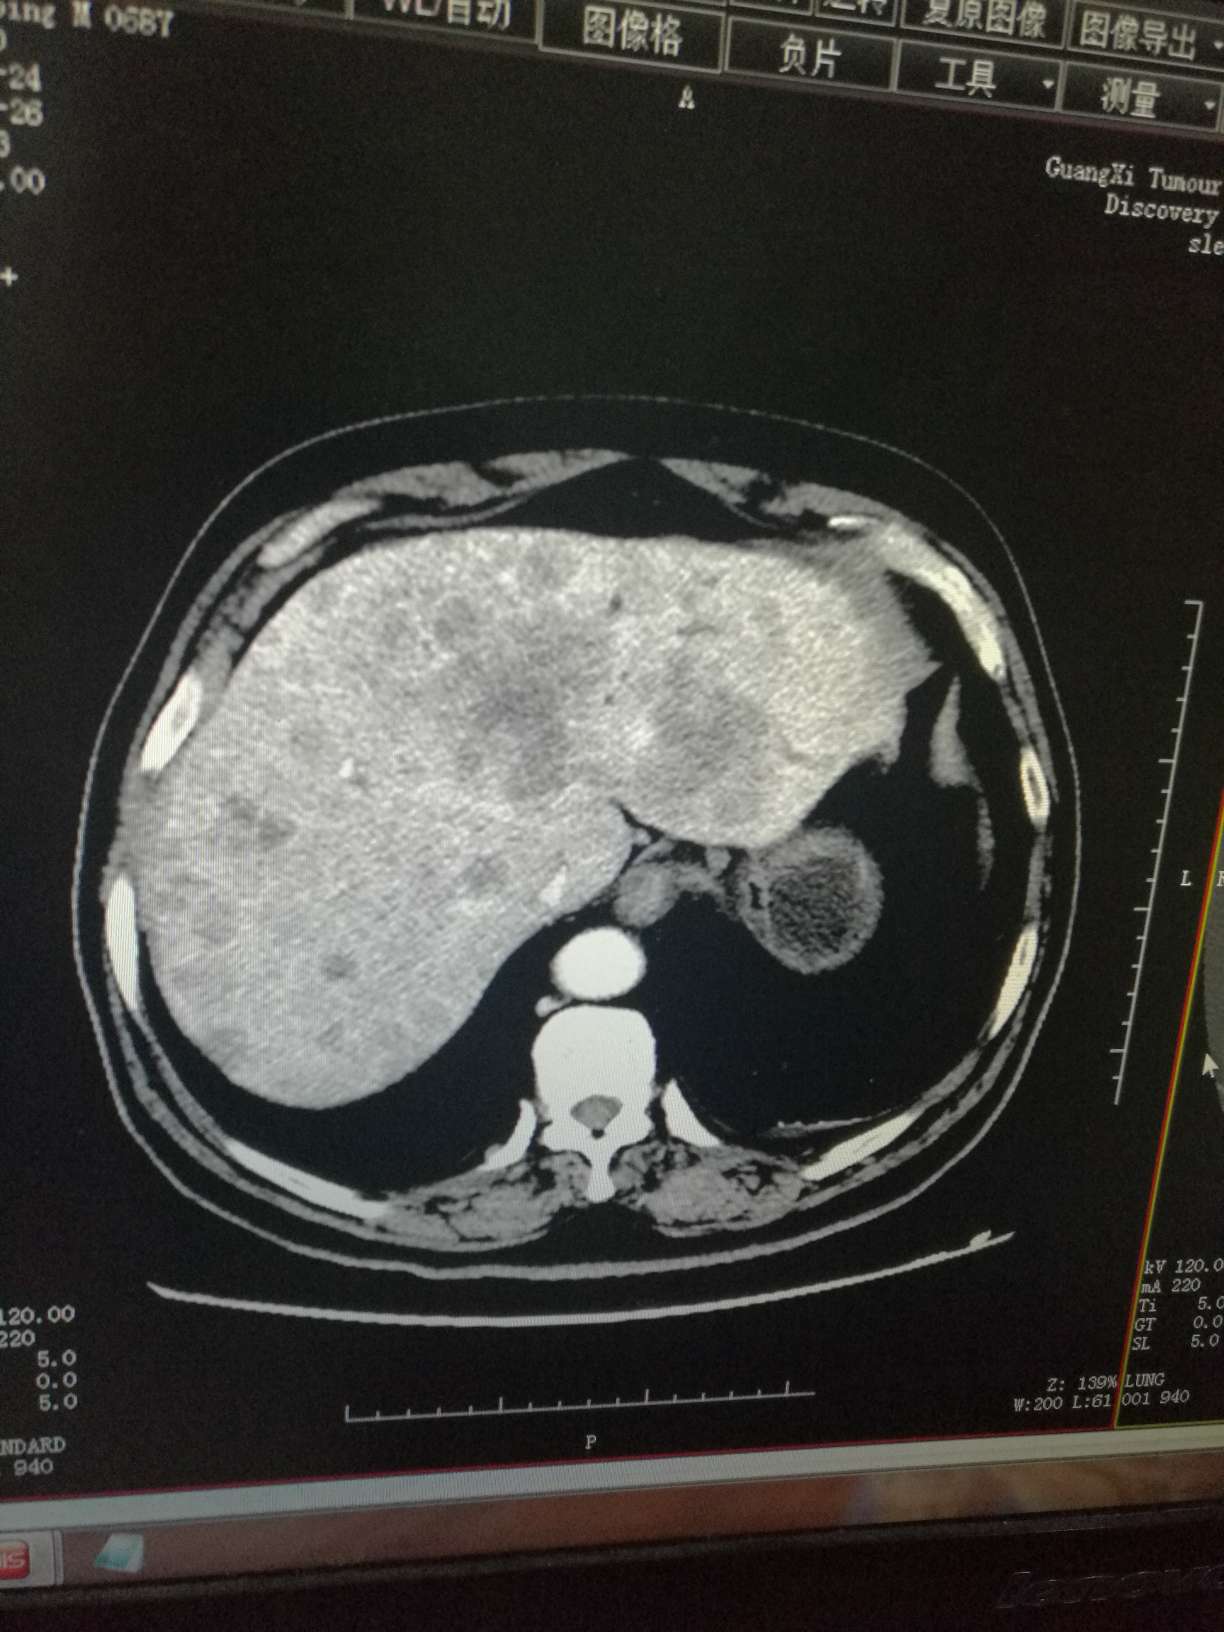

肝部阴影多了很多,骨转,肾上腺都有,同时疑似有脑转,肿瘤标志物数值也升幅很大

肝部阴影多了很多,骨转,肾上腺都有,同时疑似有脑转,肿瘤标志物数值也升幅很大